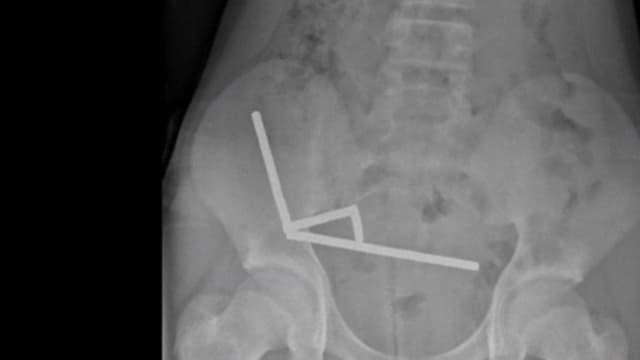

ニュージーランドで、13歳じゅうさんさいの男おとこの子こが強つよい磁石じしゃくを80個こぐらい飲のみました。

お腹なかが痛いたくなって、病院びょういんで腸ちょうの一部いちぶを切きる手術しゅじゅつを受うけました。

男おとこの子こが飲のんだのは、ネオジム磁石じしゃくです。

とても強つよい磁石じしゃくで、大人おとなが使つかうために売うっています。

飲のむと、磁石じしゃくが腸ちょうなどを引ひっ張ぱって、穴あながあいたり、死しんでしまったりすることがあります。